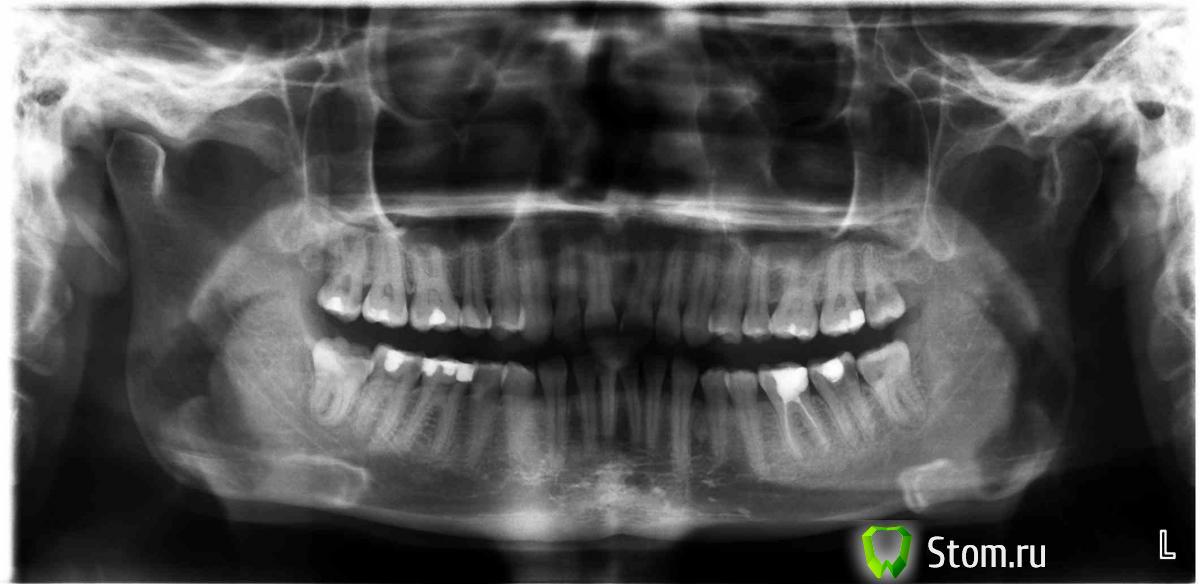

malachite Опубликовано 10 января, 2012 Поделиться Опубликовано 10 января, 2012 Добрый день. Объясняю суть своей проблемы: у меня в шестерке справа снизу глубокий пульпит. Врач пытался начать его лечить, но не смог его "заморозить". Делали анестезию септонест 1 к 200 и 1 к 100. Анестезия действует, вся правая часть лица замораживается, но зуб чувствует даже просто холодный воздух. Врач сказал, что это самая сильная анестезия, которую она может сделать (там и проводниковая и местно около зуба она делала укол несколько раз). Врач предложил 2 варианта: или общая анестезия или ждать пока нерв сам отомрет. Я выбрала второе, пока зуб сильно не болел, а только ныл немного раз в неделю. Сейчас зуб болит уже пятый день и я уже не обхожусь без анальгетиков. С каждым днем болит все сильнее. Терпеть больше не могу. Надо что-то делать. Посоветуйте, пожалуйста, какие у меня есть варианты. Живу в Санкт-Петербурге. Во вложении панорамный снимок зубов (до удаления двух восьмерок). Очень жду советов. P.S.Недавно делала алергопробы на разные анестезии (подносили к пальцу какой-то прибор, кровь не брали, в меня ничего не кололи), пробы показали, что я нормально переношу только скандонест. Но я всю жизнь лечила зубы артекаином и септонестом, правда при большом содержании адреналина у меня начинается тахикардия. Недавно удалили 2 зуба мудрости ультракаином. Ссылка на комментарий